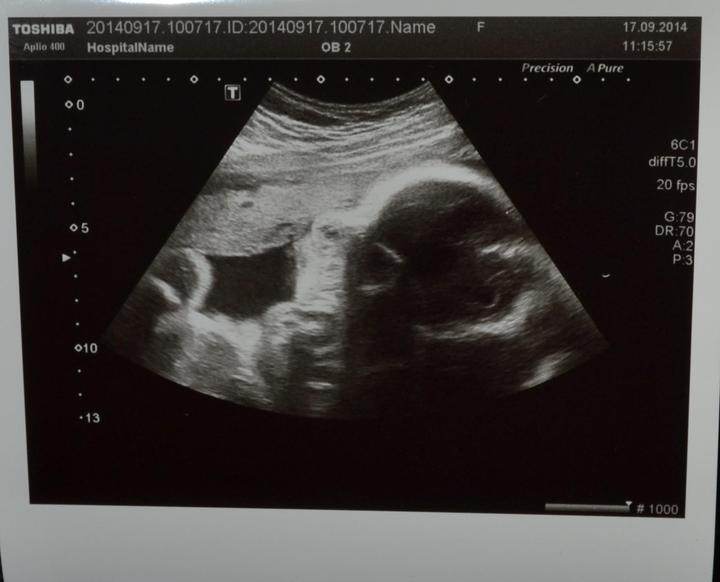

Dnešní poradna dopadla moc dobře. Ella odpovídá přesně 24+4, má dostatek plodové vody, je aktivní, srdíčko zase krásně tlouklo. Zatím je hlavičkou nahoru, ale je prý ještě čas.